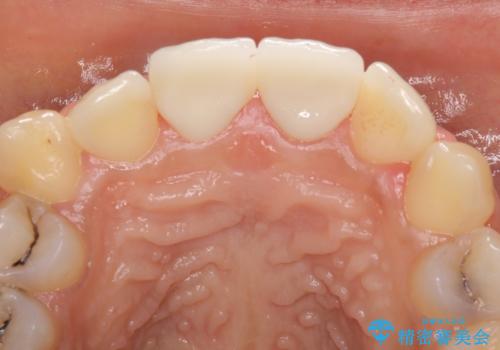

- 上の前歯2本の審美障害を気にして来院された患者様です。樹脂が無造作に充填されており、色合いも形態も不自然で、歯肉も腫れているため、オールセラミッククラウンにて補綴することとしました。

充填されたレジンを取り除いたところ、歯肉の炎症による出血が認められました。セラミッククラウン装着後は歯肉が腫れることもなく、仕上がりも自然な歯のようになり、患者様には大変満足していただきました。